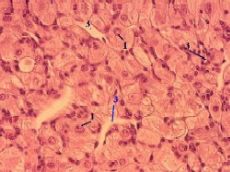

| 3,а-в. Препарат - яичник животного, жёлтое тело беременности. Окраска гематоксилин-эозином. | ||

| Лютеиновые клетки | а) Главный компонент жёлтого тела – лютеиновые клетки (1), которые лежат практически сплошной массой. б) Данные клетки: | |

крупные, округлые, имеют ячеистую цитоплазму (подобно клеткам пучковой зоны коры надпочечников, тема 22) – из-за наличия липидных включений, связанных со стероидогенезом; кроме того, содержат жёлтый пигмент (лютеин), давший название всему телу. | ||

| Строма | а) Между лютеиновыми клетками находятся прослойки соединительной ткани (2), многочисленные капилляры (3) и более крупные кровеносные сосуды (4). | |

| б) В целом жёлтое тело окружено волокнистой соединительной тканью. |